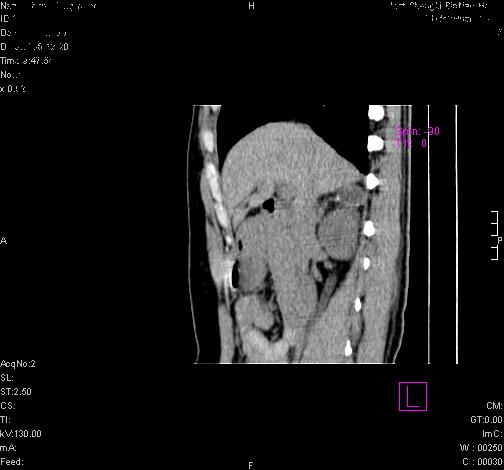

标题: CL0340:【】肾上腺囊肿,比较典型。

患者为年轻女性,查体发现右侧肾上腺囊性占位。无临床体征。

“肾上腺囊肿组织学分为4类:1)内皮细胞性,2)假性囊肿,3)寄生虫性,4)上皮细胞性。其中内皮细胞性最为常见。假性囊肿多为肾上腺内出血后遗留囊腔,囊壁无上皮细胞。寄生虫性多为包虫病引起。上皮性则很少见。”

这么明显的弧形钙化,多考虑包虫病所致的寄生虫性囊肿。

右侧肾上腺囊性密度灶囊壁有钙化。考虑肾上腺囊肿,结核?